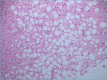

Non-alcoholic fatty liver disease (NAFLD) encompasses a spectrum of different conditions which are characterized by hepatic steatosis in the absence of secondary causes. It is currently the most common chronic liver disease worldwide, and its estimated prevalence is about 1.5-6.5%. The only histological finding of steatosis ("simple" steatosis) represents the uncomplicated form of NAFLD, while non-alcoholic steatohepatitis (NASH) is its inflammatory subtype associated with disease progression to cirrhosis and hepatocellular carcinoma (HCC), and represents the major indication for liver transplantation. NASH is still a diagnostic and therapeutic challenge for clinicians and liver biopsy is currently the only accepted method to reliably distinguish NASH from "simple" steatosis. From the histological perspectives, NAFLD and NASH continue to be an area of active interest for pathologists, with a specific focus on better methods of evaluation, morphologic clues to pathogenesis, and predictors of fibrosis progression. This review focuses on histopathology of NAFLD in adults, with the aim to provide a practical diagnostic approach useful in the clinical routine.